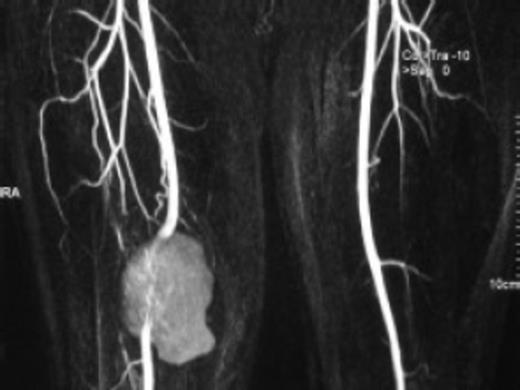

CT angiogram was done which showed a pseudoaneurysm of the lower third of femoral artery.

CT angiogram showed a pseudoaneurysm of the lower third of femoral artery